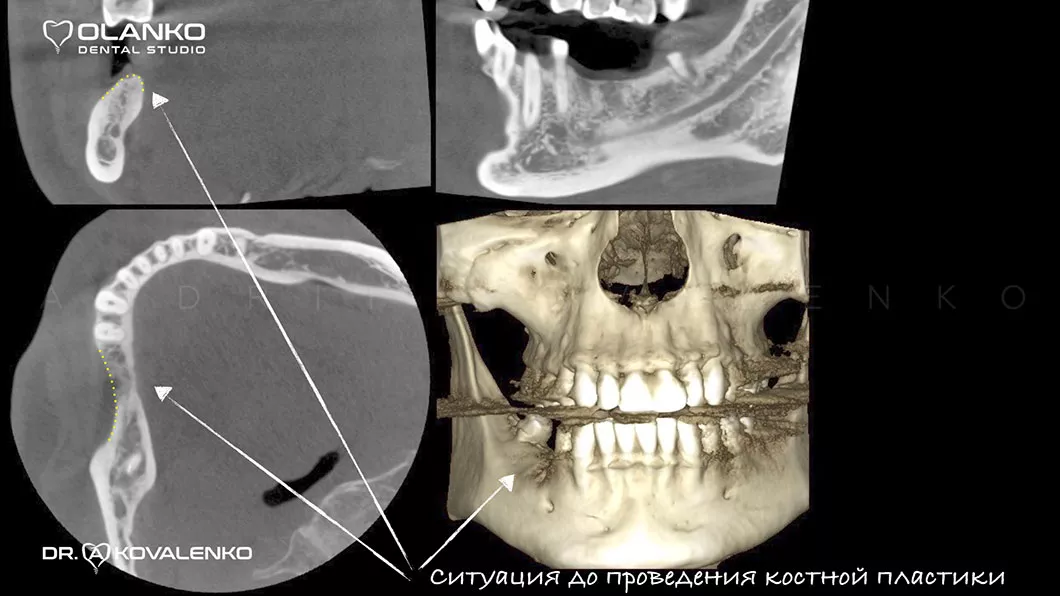

Вигляд щелепної кістки на 3D знімку до операції нарощування кістки

Вигляд  щелепної кістки на 3D знімку до операції нарощування кістки Оланко Бровари Київ

Вигляд  щелепної кістки на 3D знімку Оланко Бровари Київ